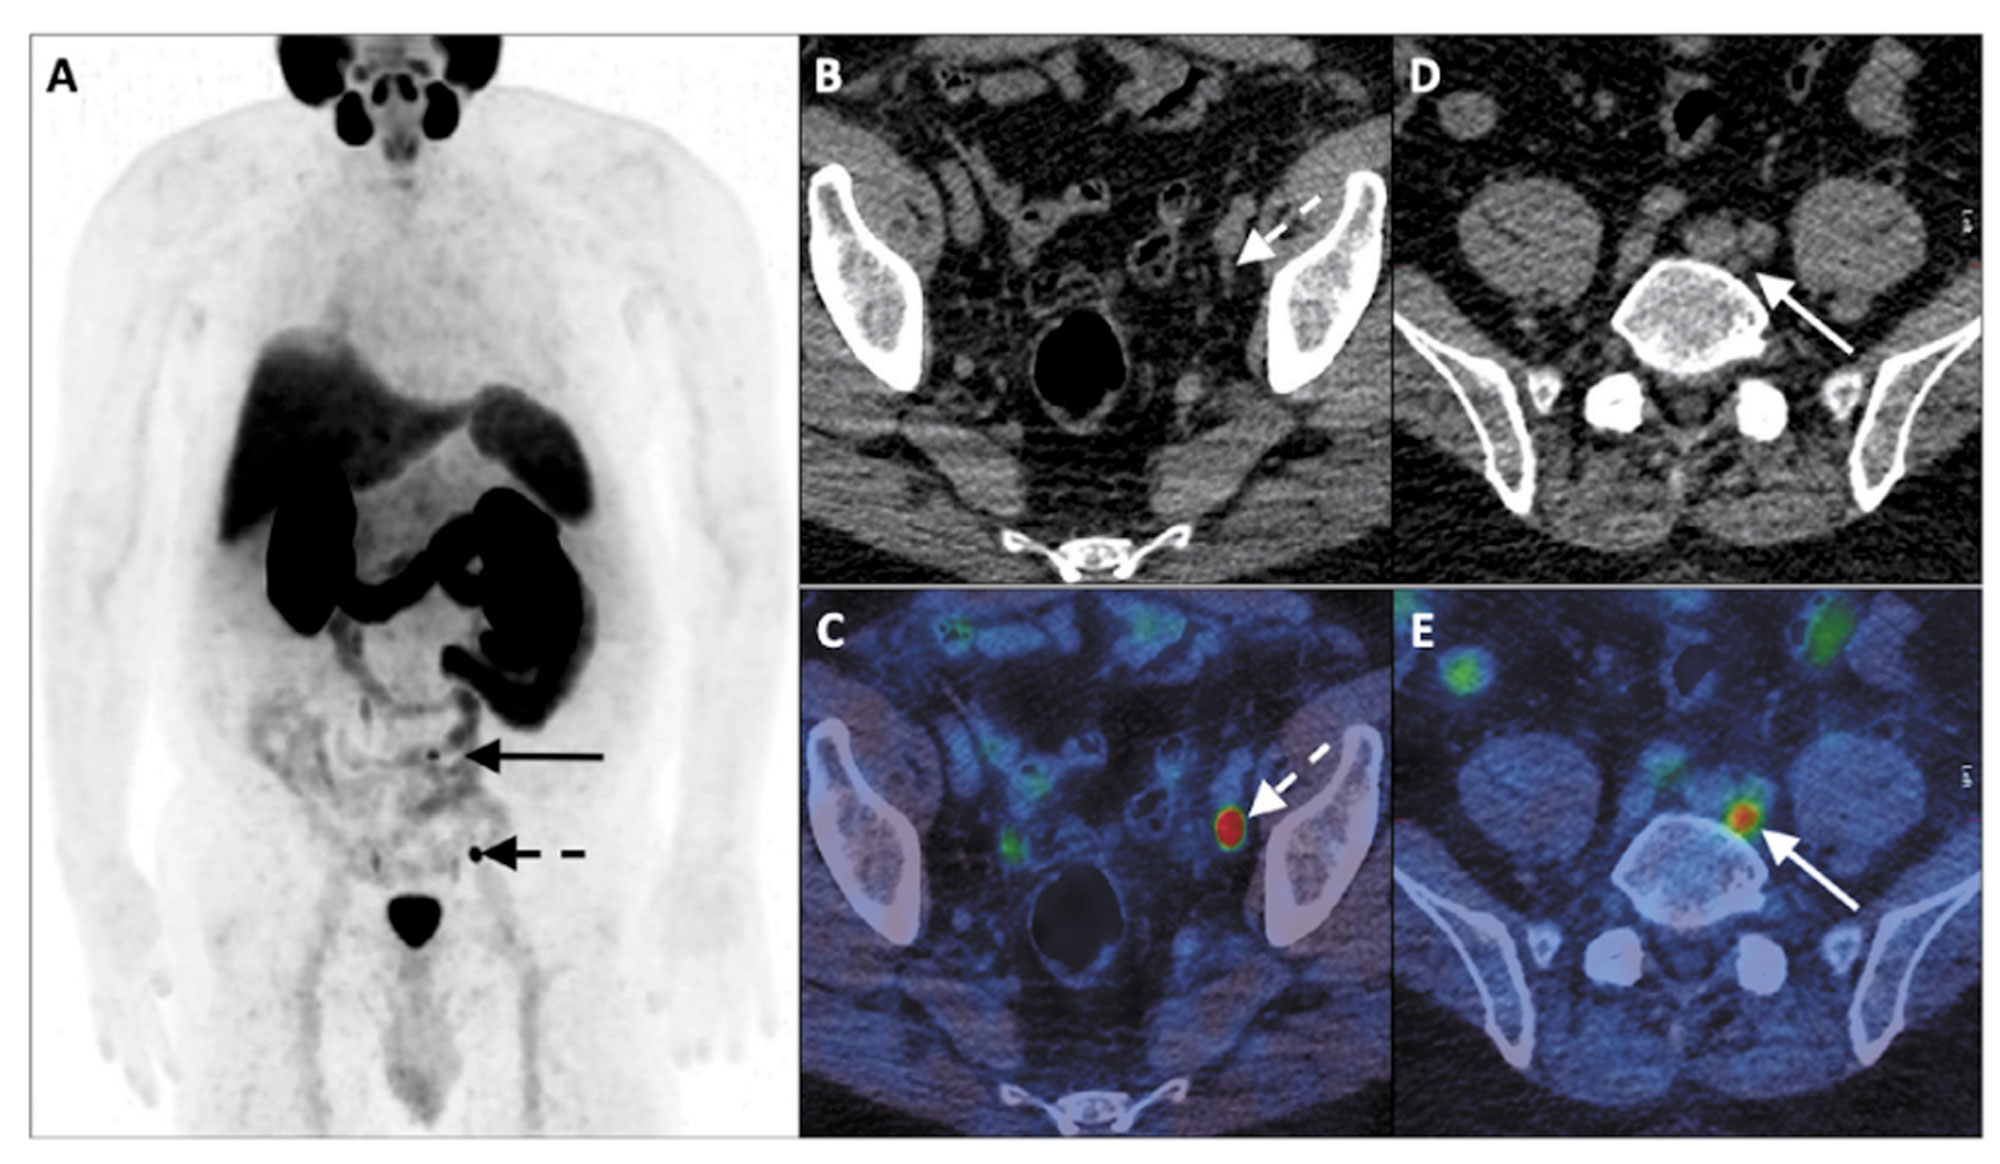

Figure 3: 68Ga-PSMA-11 PET-CT in the biochemical recurrence setting. GS 3 + 4 CaP,

post-RP (pT2N0M0) with PSA rise to 3.7ng/mL.

A: PET B & D: Axial CT C & E: Fused PET-CT

Images demonstrate an intensely PSMA avid 6mm external iliac node and

moderately PSMA avid 6mm left common iliac node.

Standard imaging with bone scan and MRI has a low pick-up rate in men with a PSA below 2ng/mL. However, PSMA PET/CT has been shown to identify residual cancer with positivity rates of 33%, 46%, 57%, 82%, and 97%, in men with post-RP PSA ranges of 0-0.19, 0.2-0.49, 0.5-0.99, 1-1.99, and >2ng/mL, respectively.

68Ga-PSMA PET-CT has also demonstrated its superiority to conventional imaging and indeed other PET radiopharmaceuticals in BCR, particularly at low PSA levels. Detection rates of between 11.3-58.3% at PSA levels <0.ng/ml and 11.0-65.0% at PSA levels <0.5ng/ml have been reported [15].

In a meta-analysis conducted by Pereira et al. pooled detection rates of 33% PSA <0.2ng/ml, 45% PSA 0.2-0.5ng/ml, 95% >2.0ng/ml were reported, with similar results by Hope et al, which included only studies with histological validation, demonstrating a pooled sensitivity of 99%, specificity of 76% and a 40% detection rate at a PSA level <0.2ng/ml [16,17].